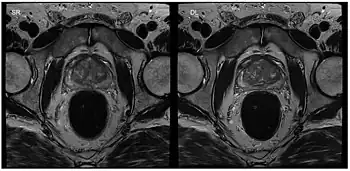

Applications in interventional MRI, which refers to the monitoring of minimally invasive surgical procedures, are possible by interactively changing parameters such as image position and orientation. This application is particularly helpful when a 3D image of the tissue is needed during surgery.[10] It requires an in-room display for the physician to use during the procedure as well as the use of MRI-safe surgical tools. These include ceramic, plastic, or titanium, which is a paramagnetic metal. By using bSSFP and parallel imaging with multiple coils, frame rates of 5-10 frames per second have been accomplished, allowing for the visualization of cardiac procedures.[10]